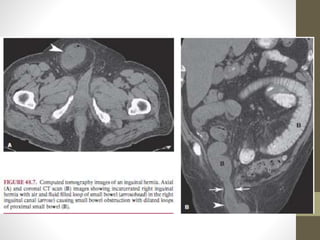

Hernias

• Segunda causa mas frecuente en países occidentales

• Síntomas de obstrucción: Hernia femoral o inguinal.

• Hernias femorales:

• Encarcelación.

• Necrosis intestinal

• Tamaño pequeño

• Hernias internas: Laparoscopia.

• Hernias del obturador.

• Hernias Paraduodenales

• Identificar tipo de hernia y compromiso.

• Antibioticoterpia, reducción de hernia, evaluar viabilidad

intestinal.

• Hernia de Richter:

• Obstruccion incompleta.

• Encarcelamiento y estrangulación de una porción intestinal.

• >50% completa

Hernias • Segunda causamas frecuente en países occidentales • Síntomas de obstrucción: Hernia femoral o inguinal. • Hernias femorales: • Encarcelación. • Necrosis intestinal • Tamaño pequeño • Hernias internas: Laparoscopia. • Hernias del obturador. • Hernias Paraduodenales

• Identificar tipode hernia y compromiso. • Antibioticoterpia, reducción de hernia, evaluar viabilidad intestinal. • Hernia de Richter: • Obstruccion incompleta. • Encarcelamiento y estrangulación de una porción intestinal. • >50% completa